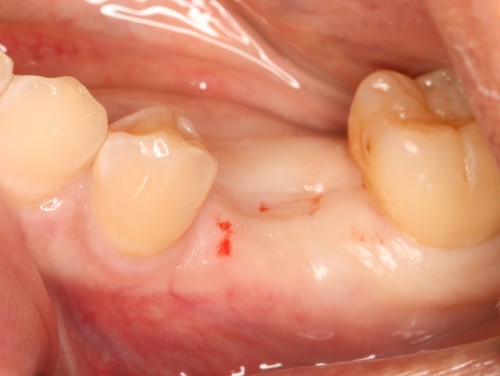

術前

左下5部 乳歯晩期残存

抜歯後

インプラント埋入直前

インプラント埋入直後

埋入後約3ヶ月

オペ時のISQ値

土台装着

被せ物装着

被せ物装着後